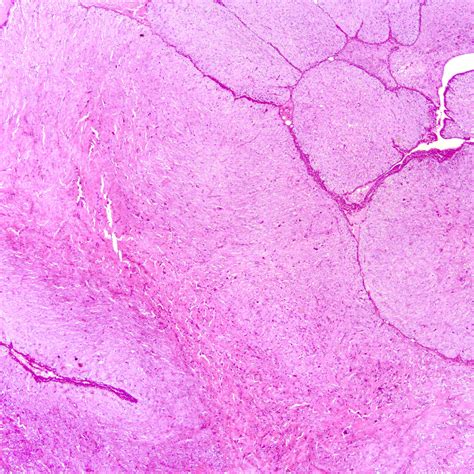

Malignant phyllodes tumors are the least common but most aggressive type. They are characterized by marked stromal overgrowth, increased cellularity, and the presence of stromal sarcoma. These tumors have a higher risk of local recurrence and distant metastasis, making early detection and aggressive treatment essential.

Histopathological analysis is the gold standard for diagnosing phyllodes tumors. A core needle biopsy or excisional biopsy is performed to obtain a tissue sample for microscopic examination. The histopathological features, including stromal overgrowth, epithelial components, and cellularity, are evaluated to determine the tumor's type and grade.